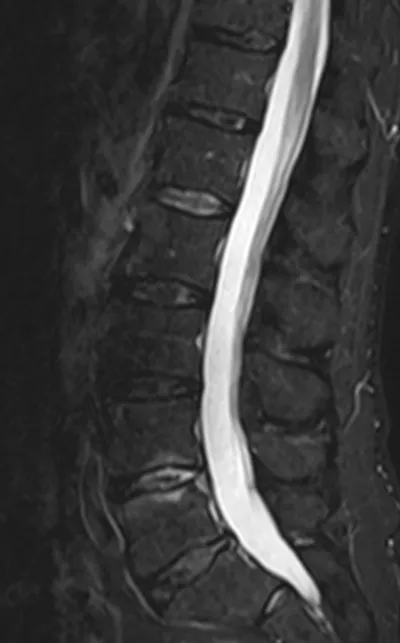

This collection contains 1 radiology images related to infection, including various imaging modalities such as X-rays, MRIs, CT scans, and ultrasound images commonly used in medical diagnosis and education.